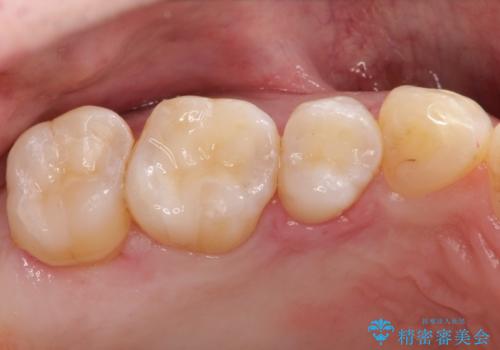

メタルフリーの治療 メタルインレーからセラミックインレーへ

セラミックインレーに治療を行っております。

e-max プレスインレーにて修復治療を行っているため適合性及び審美性の高い治療を行うことができます